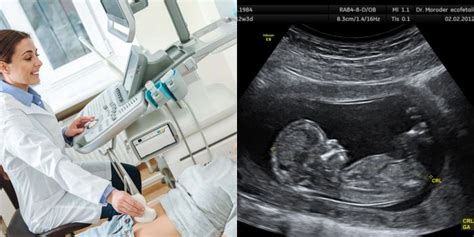

Pirmasis akušerinio patikrinimo vizitas ir pirmoji echoskopija yra rekomenduojami praėjus septynioms ar aštuonioms savaitėms po paskutinių mėnesinių datos. Pirmoji echoskopija yra labai svarbi, nes ji padeda patvirtinti embrionų buvimą ir skaičių gimdoje bei tiksliai nustatyti nėštumo trukmę.

- Pirmoji echoskopija (7-8 savaitės): Kaip minėta, šis tyrimas atliekamas ankstyvame nėštumo etape, siekiant patvirtinti nėštumą, nustatyti jo trukmę ir patikrinti, ar nėra galimų komplikacijų.

- Antrojo Trimestro Echoskopija (19-21 savaitės): Ši echoskopija, dar žinoma kaip morfologinė echoskopija, yra itin svarbi. Ji leidžia gydytojui detaliai išstudijuoti vaisiaus morfologiją ir atmesti galimus įgimtus apsigimimus.

- Trečiojo Trimestro Echoskopija: Tradiciškai trečiojo trimestro echoskopija buvo siūloma visoms nėščiosioms. Tačiau naujausios rekomendacijos numato, kad ji atliekama tik toms moterims, kurioms gydytojas nustato motinos ar vaisiaus patologiją, dėl kurios yra būtinas papildomas echoskopinis tyrimas. Nors nacionalinės ir tarptautinės gairės paprastai rekomenduoja dvi echoskopijas nėštumo metu, jei nėra komplikacijų, individualios situacijos gali reikalauti daugiau tyrimų.